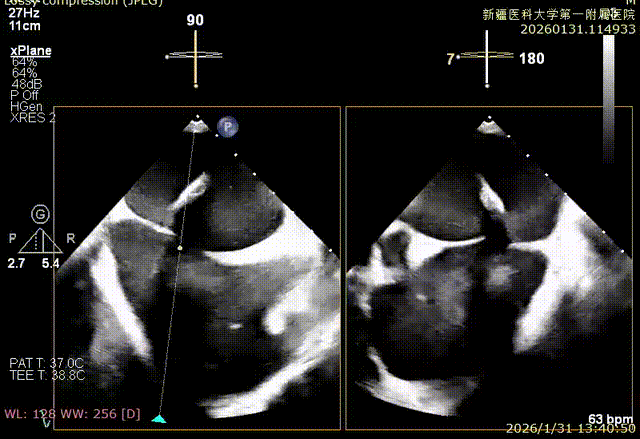

XPLAN切面2区后叶栓系

XPLAN切面中重度反流

3D enface 切面

3D enface观察反流